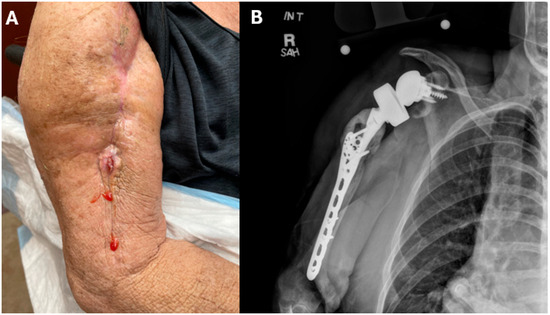

Over the subsequent months, the patient reported ongoing and worsening purulent drainage from her right shoulder (Figure 1A). An X-ray of the shoulder demonstrated soft tissue swelling around the prosthesis (Figure 1B). Surgical exploration was performed. Purulence was encountered around the destination spacer. The shoulder prosthesis, proximal humeral plate, and antibiotic cement were completely removed. Cement impregnated with vancomycin and gentamicin was applied to the glenoid; an antifungal agent was not included in the cement. Five separate tissue specimens were plated on selective fungal media, with the growth of small cream colonies that were identified on MALDI-TOF as Candida glabrata. The patient was started on micafungin 100 mg IV q 24 h post-operatively. Itraconazole 100 mg orally twice daily was added two weeks later after the initial susceptibilities, obtained using a Sensititre® Y09 microtiter plate with a colorimetric endpoint (Thermo Fisher Scientific, Waltham, MA, USA), demonstrated an intermediate susceptibility to micafungin (Table 1).

Figure 1. Right shoulder periprosthetic joint infection. (A) Image of right shoulder with purulent drainage at site of previous arthroplasty scar. (B) X-ray of right shoulder demonstrating significant soft tissue swelling.